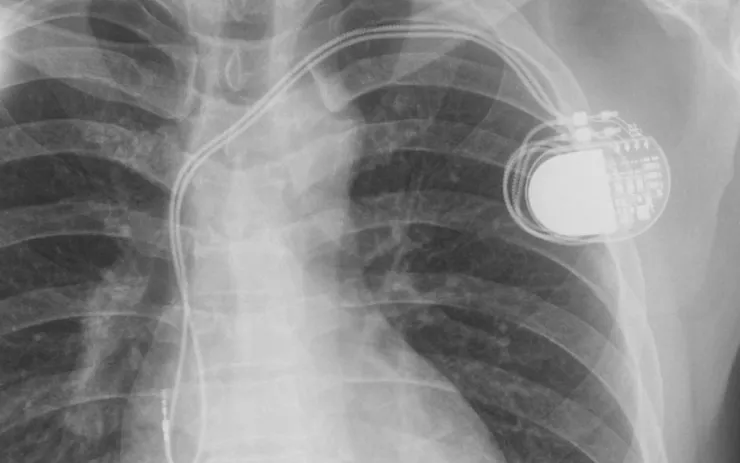

Hình minh họa.

Sau hội chẩn, ekip quyết định đặt máy tạo nhịp tim vĩnh viễn nhằm duy trì nhịp tim ổn định. Tuy nhiên, đây là ca bệnh đặc biệt phức tạp khi bệnh nhân mắc suy thận mạn và đã chạy thận nhân tạo liên tục 17 năm tại Bệnh viện Đa khoa Ninh Thuận. Quá trình điều trị kéo dài khiến hệ thống mạch máu bị hẹp và biến đổi, gây nhiều khó khăn khi đưa điện cực vào tim.

Nhờ sự chuẩn bị kỹ lưỡng và kinh nghiệm chuyên môn, ca can thiệp đã được thực hiện thành công. Sau đặt máy, tình trạng bệnh nhân cải thiện rõ rệt, có thể vận động nhẹ và không còn các cơn ngất nguy hiểm.